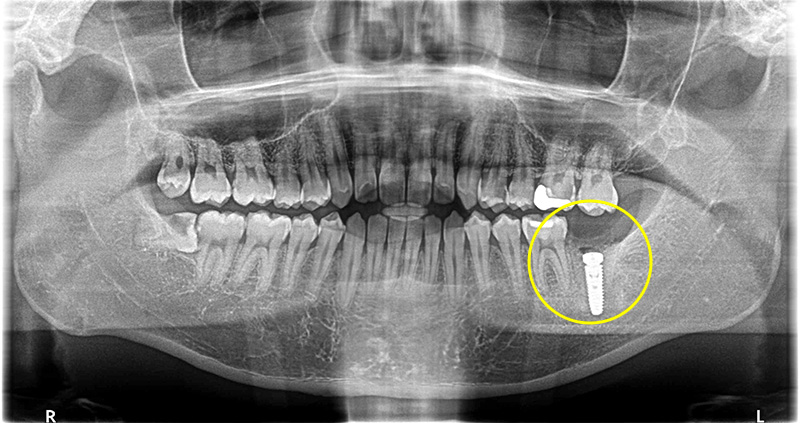

レントゲンでの検査の結果、歯根に破折線が見られた為、保存不可であることがわかりました。

破折のため膿が大きく骨欠損の範囲が大きかったためインプラントの持ちを良くするため骨造成も同時に行っています。